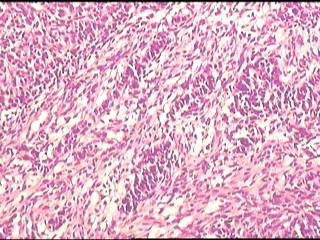

•25岁,女性,停经35周,发现腹腔包块1月余。

•手术所见:右侧卵巢肿瘤,12×8.6×8.0cm大小,表面光滑,内实质似鱼肉样、部分区域胶冻状,伴少许盆腔积水。

• 卵巢肿瘤图1

图1

性索间质来源的肿瘤。

先考虑卵泡膜

硬化性间质瘤